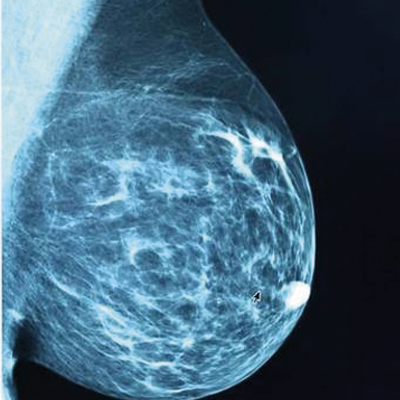

Mamografía

(MG)